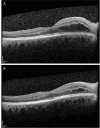

Membranous glomerulonephritis is the leading cause of nephrotic syndrome in non-diabetic Caucasian adults. For patients at risk of progressing to end-stage renal disease, immunosuppression, particularly rituximab, is the recommended treatment. While extremely rare, cases of cystoid macular edema associated with rituximab have been documented in the literature. In this report, we present the case of a 54-year-old male with membranous glomerulonephritis at a high risk of progressing to end-stage renal disease who experienced cystoid macular edema hours after receiving rituximab infusion. Following the discontinuation of the medication, the patient spontaneously recovered visual acuity without the need for any targeted therapy.